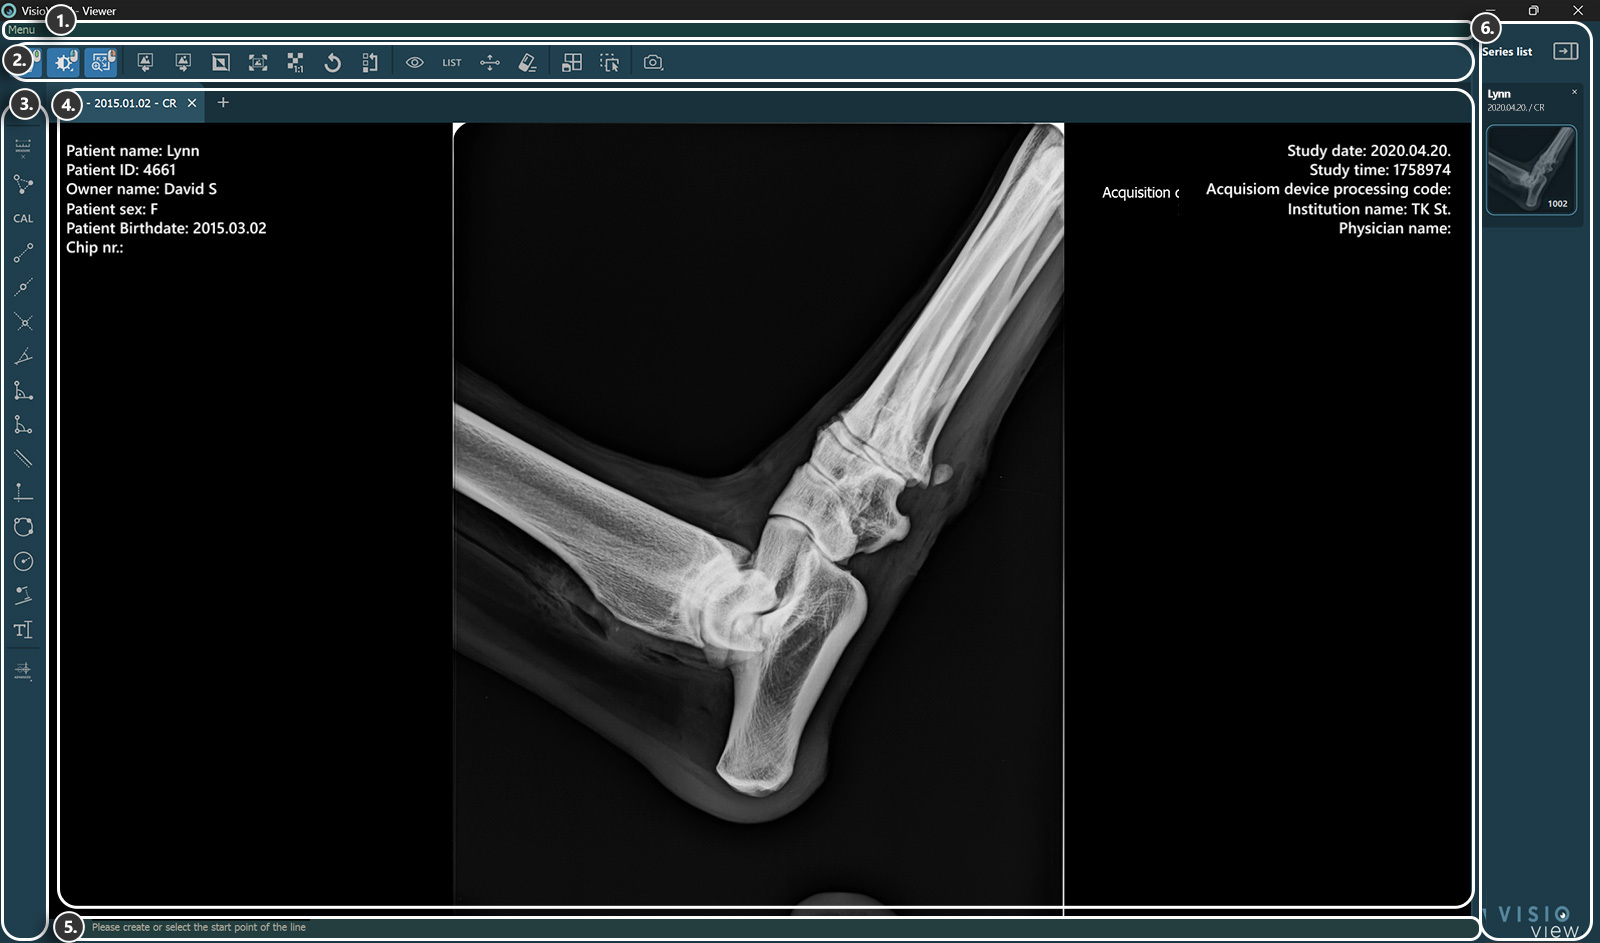

A VisioVIEW Megjelenítő szakaszai¶

A VisioVIEW Megjelenítő több szakaszból áll, amelyek mindegyike egy adott célnak felel meg. Az alábbiakban az egyes szakaszok részletes leírása található.

Megjelenítő felület¶

Beteginformáció

Tanulmányi információk

Információs sáv¶

Információkat vagy utasításokat jelenít meg az aktuálisan kiválasztott eszközről.